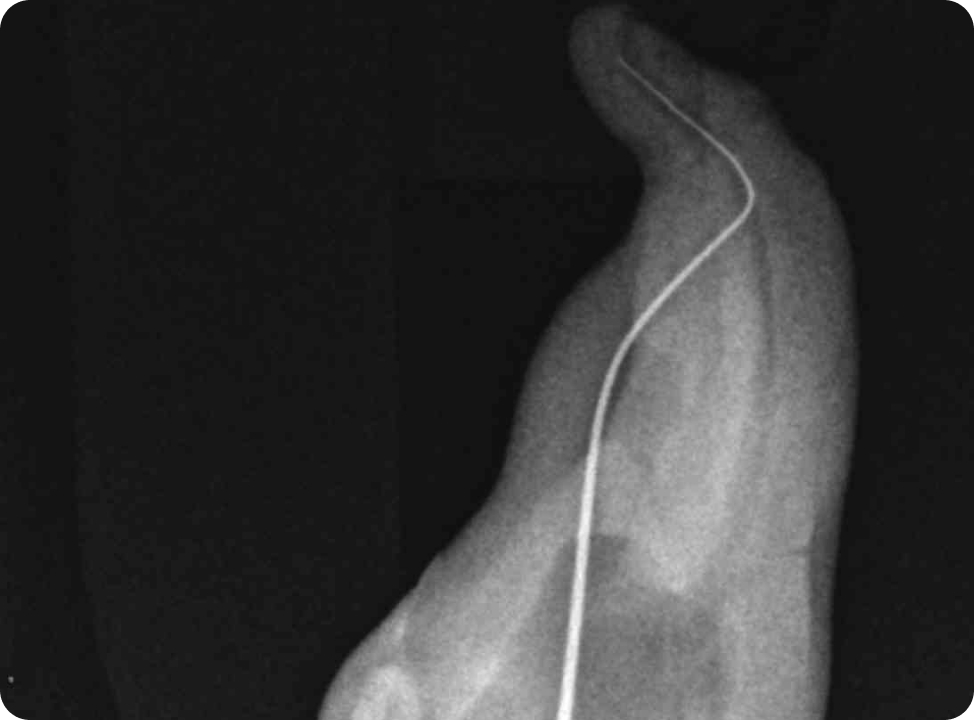

Перфорації кореневого каналу

• клініка

• діагностика

• менеджмент

Перфорації корня каналу

Класифікація перфорацій. Вплив розташування на прогноз і тактику.

Вибір матеріалу в залежності від розташування і розміру перфорації( фуркаційна, середньої третини і апікальна)

Чи є найкращий матеріал для закриття перфорації?

Правила використання композиту для закриття перфорації.

Використання біокерамічних силерів, переваги і недоліки

Сучасний «золотий стандарт» МТА? Чому МТА може не застигати? Робота з перфорацією один чи два візити? Вплив на прогноз. Відеодемонстрація роботи з різними матеріалами і різною локацією. Допоміжне обладнання при роботі з мікроскопом і без. Прогноз закриття перфорацій. Розгляд клінічних питань слухачів щодо перфорацій( підготувати клінічні ситуації). Вебінар надає 1 бал БПР,